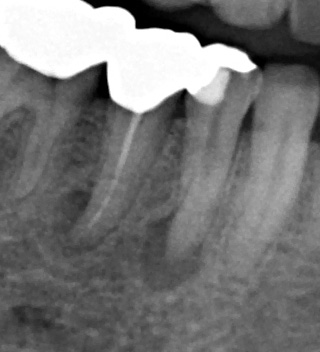

根管治療を4回行い症状がなくなったため根管充填を行いました。

垂直加圧根管充填できちっと根尖にも側枝にも充填剤が入りました。側枝に充塡剤がしっかり入っているとこのようにレントゲンに写ります(部分)。処置後3年経過しましたが快適だそうです。